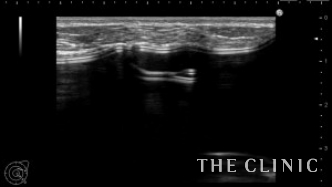

エコーではカプセルの肥厚とカプセル拘縮によるバッグの歪みを認めます。

シリコンバッグによるカプセル拘縮のエコー診断カルテ